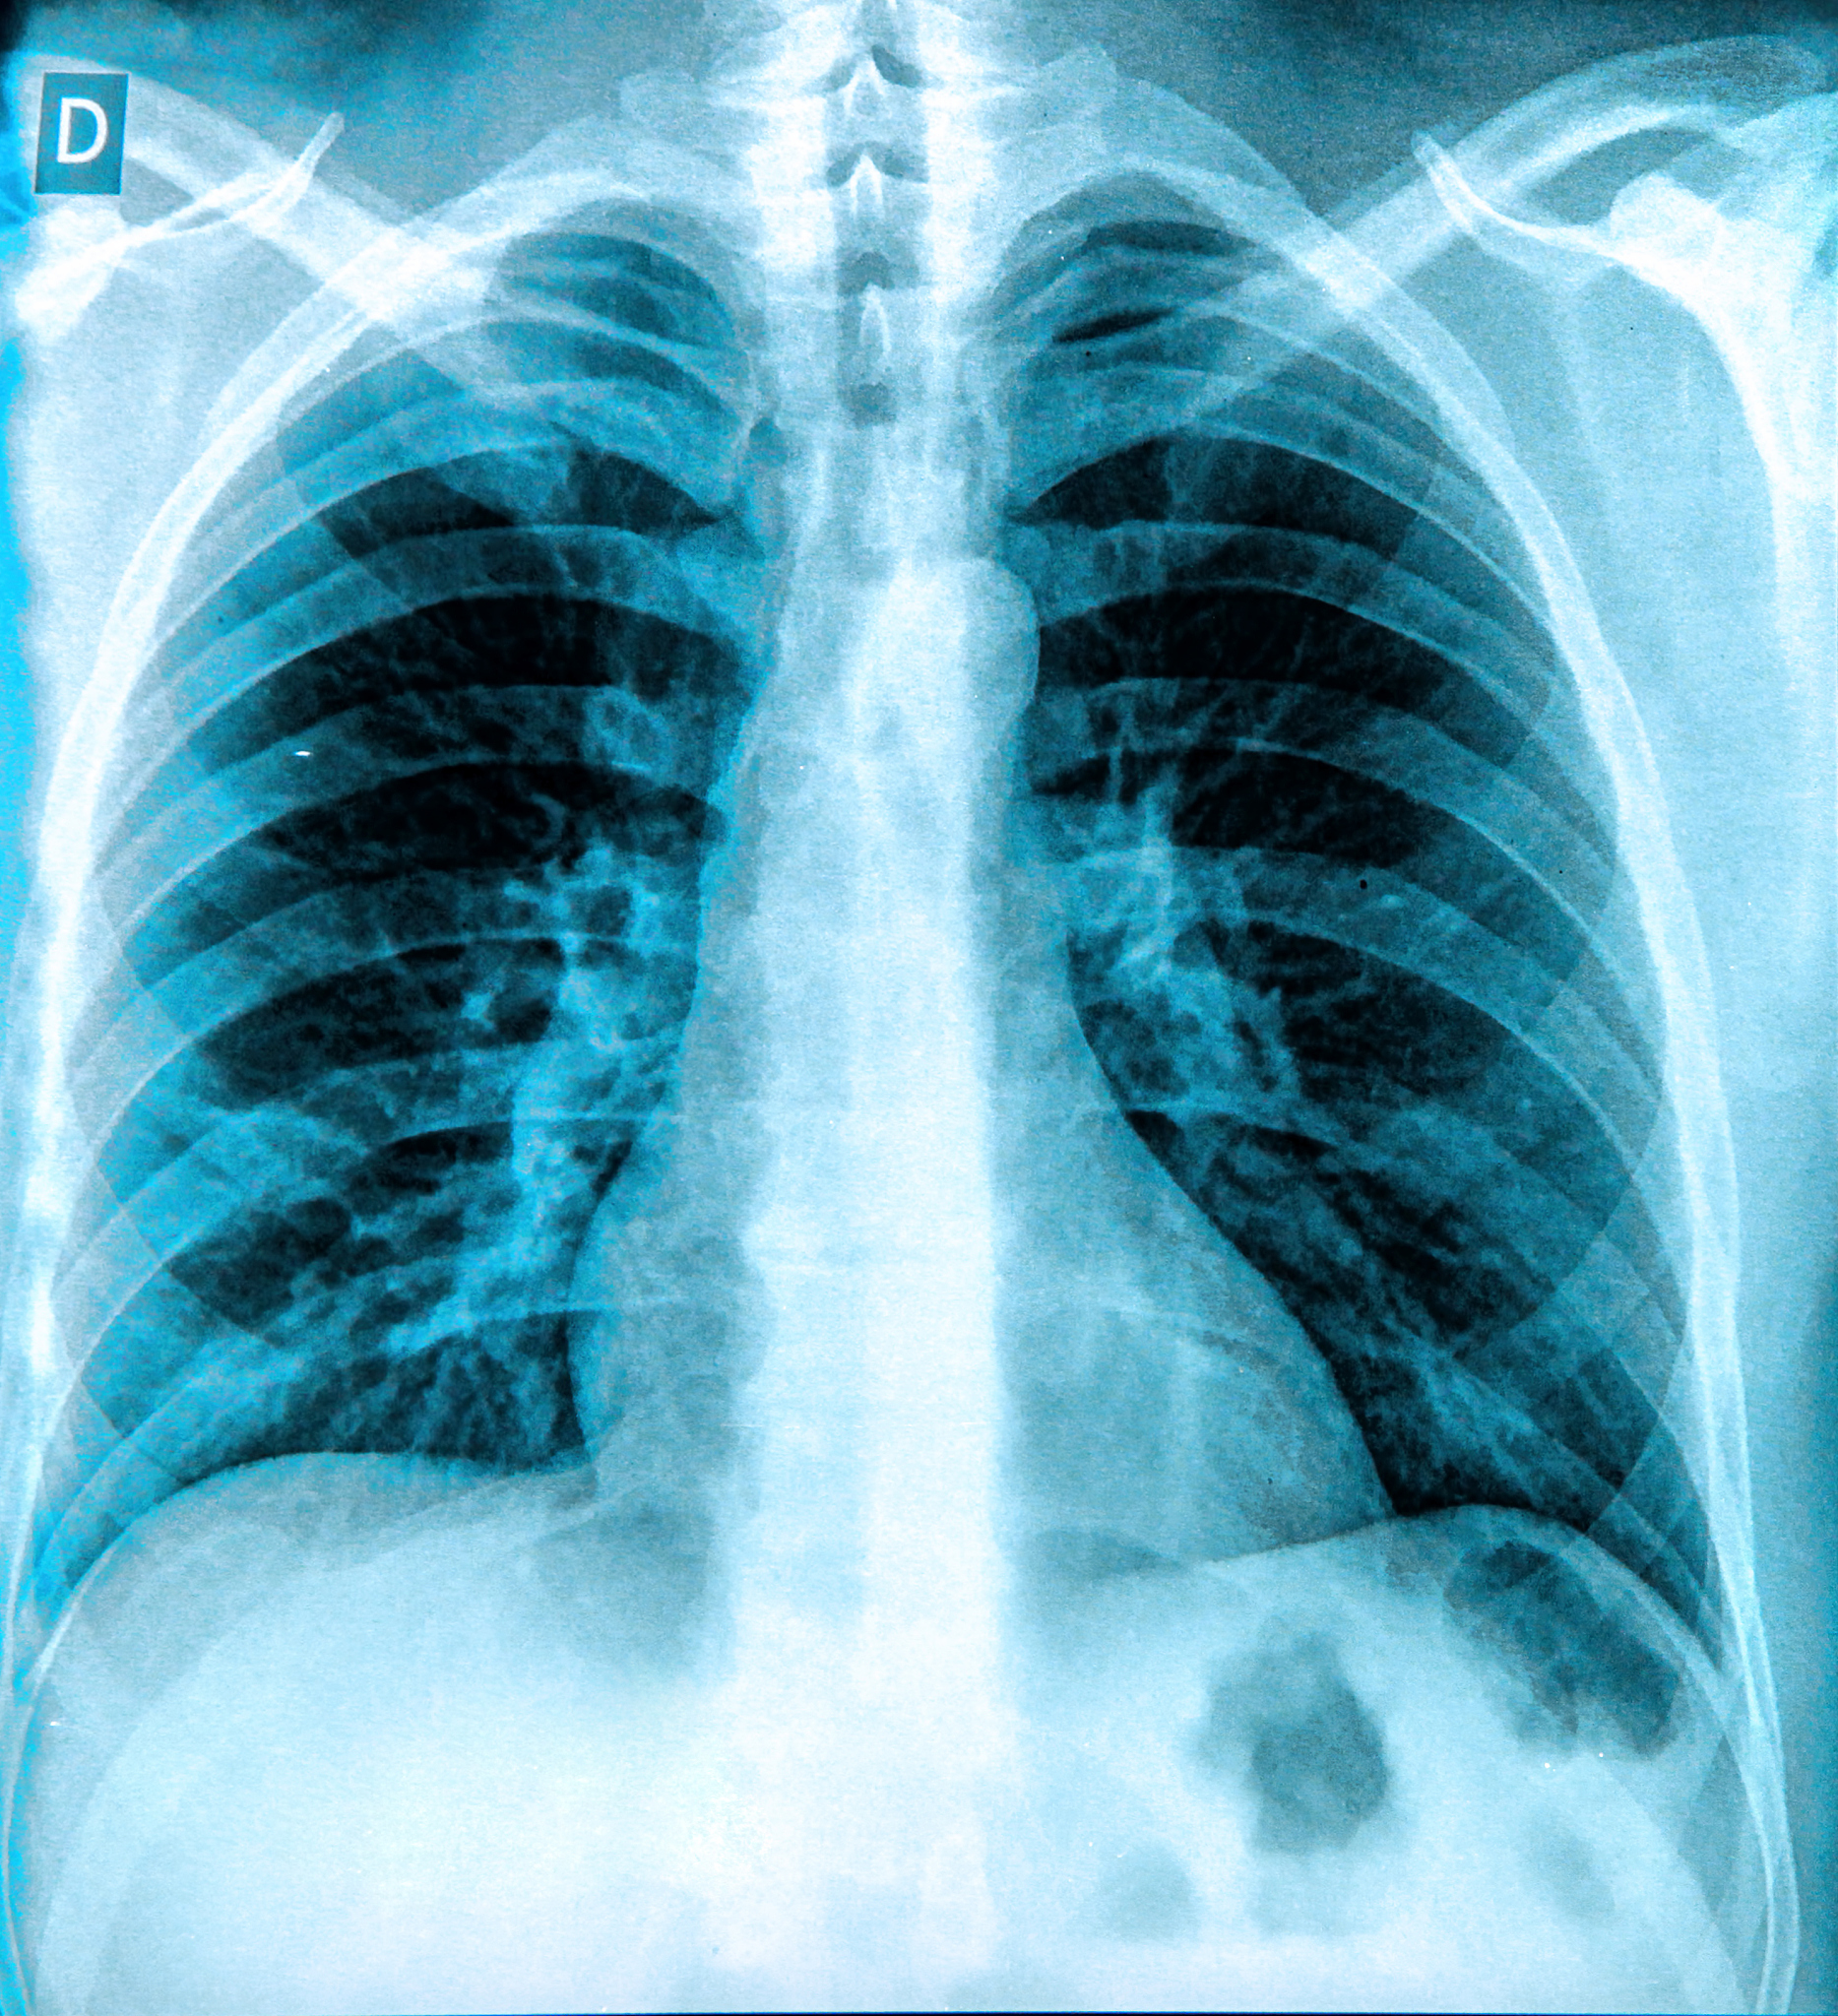

无症状性心衰的诊断需要通过心脏检查来确定心脏功能是否受损。常见的检查包括心电图、超声心动图和心肌标志物检测。如果发现心脏功能异常,但患者没有明显的症状,可能需要进一步评估病因和制定治疗方案。